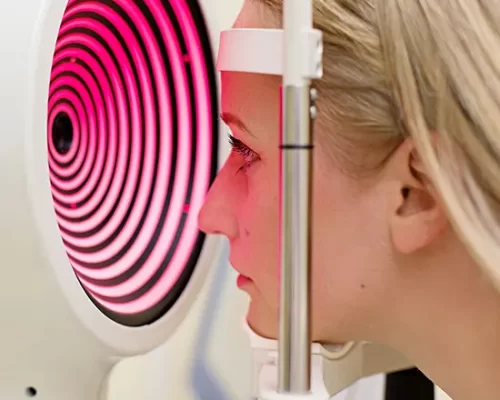

Médica Oftalmologista especialista no tratamento das doenças da retina

Mapeamento de Retina: um cuidado essencial para a saúde dos seus olhos

O mapeamento de retina é um exame fundamental para avaliar a saúde ocular de forma